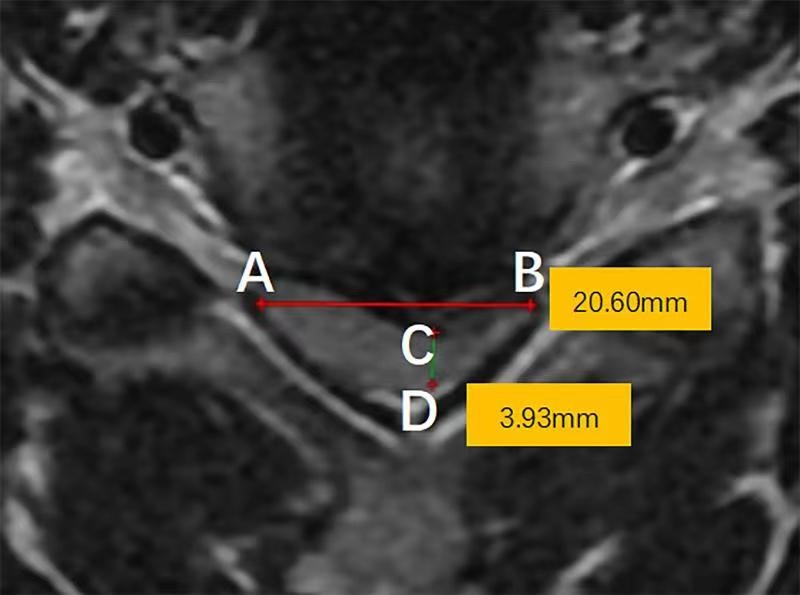

3.3 颈椎MRI轴位脊髓压迫比值

颈椎MRI轴位脊髓压迫比值为在颈椎MRI轴位像上,测量脊髓压迫最重节段前后径与横径的比值(图2)。

图2.颈椎MRI轴位脊髓压迫比值的测量方法。颈椎MRI轴位压迫程度最重节段脊髓横径(AB)与前后径(CD)